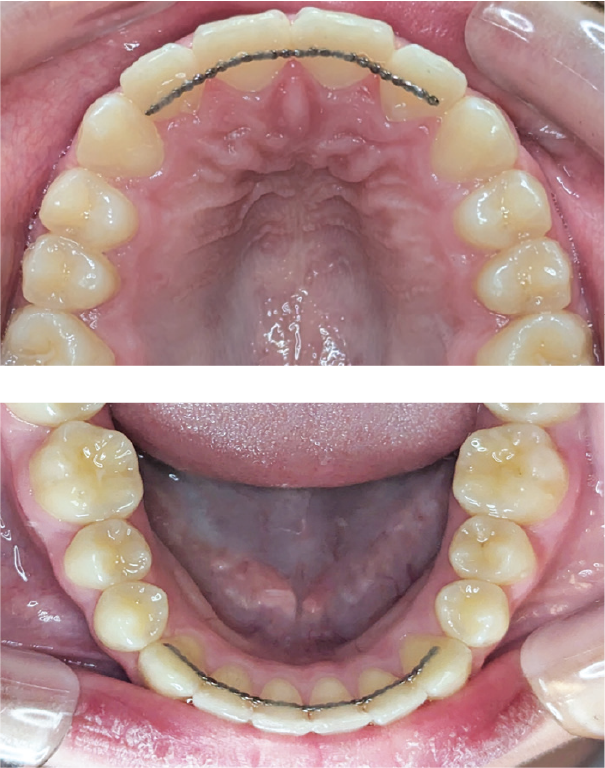

Look at the cranial bone movement that occurs when you inhale & exhale: